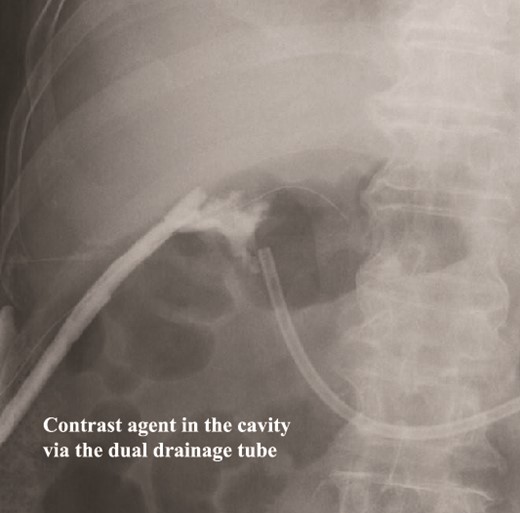

The amylase levels of drainage fluid and blood at postoperative day (POD) 1 (Ascites 6980 IU/dl, Serum 1123 IU/dl) and POD 3 (Ascites 673 IU/dl, Serum 487 IU/dl) revealed pancreatic fistula based on the criteria of International Study Group of Pancreatic Fistula [2]. After that, their results improved, and fluoroscopy showed no stenosis and leakage. Therefore, we removed all drains at POD 8, however the following day, the patient developed high fever. Plain CT revealed intraperitoneal fluid around subdiaphragmatic and duodenal stump (Fig. 3). We inserted a pig-tail drainage tube to the subdiaphragmatic space (Fig. 4). Since biliary fluid was discharged through the tube, we suspected duodenal leakage and started infusion of somatostatin analogs and antibiotics. At POD 13, the patient complained of whole abdominal pain with peritoneal signs. As the patient became hemodynamically unstable, we performed emergent laparotomy to lavage and insert multiple drainage tubes. Two perforation pinholes were identified in the anterior wall of the duodenum, near the stump. We resected the vulnerable duodenal stump including the perforation site and closed by Gambee’s method with unabsorbable 4–0 proline (Fig. 5). We inserted multiple drainage tubes (Fig. 6a): a C-tube from the cystic duct into the common bile duct to separate biliary juice and pancreatic juice, a dual drainage tube around the duodenal stump with continuous suction (Fig. 6b), a simple intraluminal drainage tube via the duodenum near the stump through a new skin incision on the left side of the abdomen for duodenal decompression, and a drainage tube into the rectovesical pouch. After the reoperation, we irrigated the cavity around the duodenal stump through each drain with saline. Since the contrast agent did not flow into the duodenum and the cavity around the duodenal stump gradually got smaller (Fig. 7), oral intake of fluid diet was initiated at POD 37. However, fistulography at POD 44 showed that the fistula of duodenal stump had relapsed (Fig. 8). Although we considered performing second reoperation for duodenal stump closure, due to the cavity around the duodenal stump was located, we continued conservative management and irrigation via drainage tubes. Fistulography demonstrated no leakage from the duodenal stump at POD 56, and the patient discharged at POD 59.

Fistulography locates the cavity, and the fistula is closed. As there was no flow of the contrast agent into the duodenum, we located the cavity around the duodenal stump.